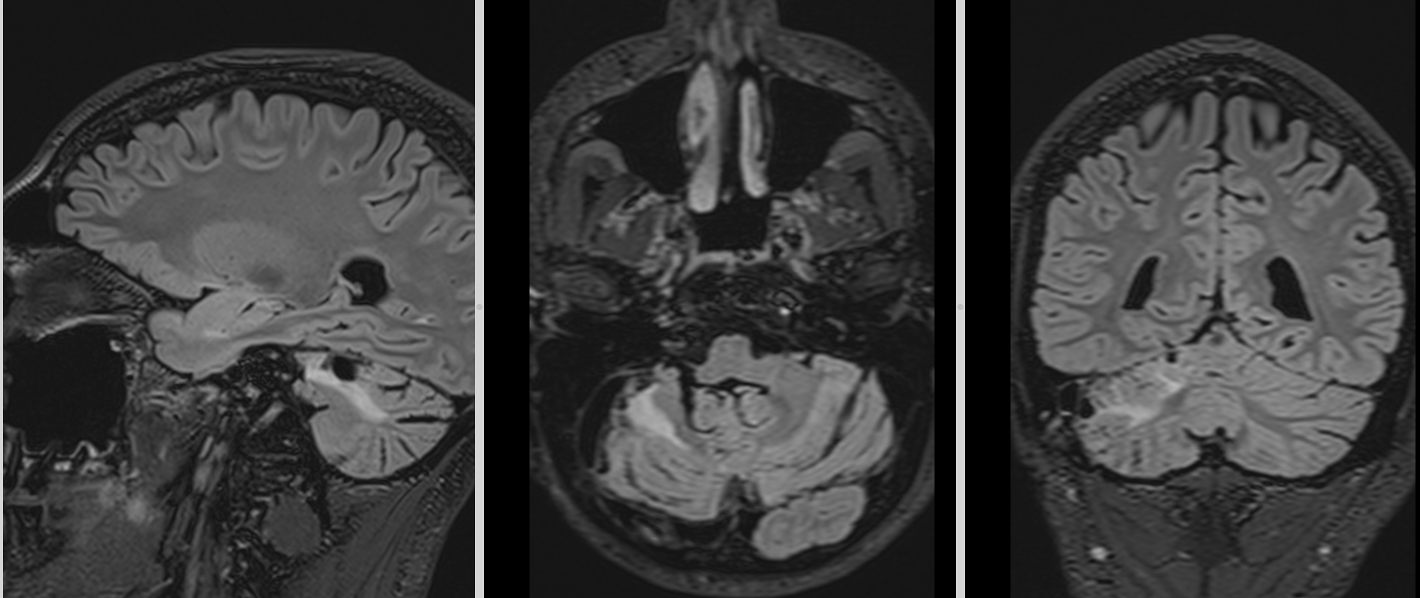

RMN cerebral

Este investigația de elecție. Meduloblastomul apare de obicei ca:

- leziune solidă, bine delimitată sau infiltrativă

- hipointensă T1, hiperintensă T2

- captare intensă de contrast

- posibilă restricție de difuzie (densitate celulară mare)

La adult, localizarea în emisfera cerebeloasă poate duce la confuzie cu alte tumori (metastaze, hemangioblastom, astrocitom).